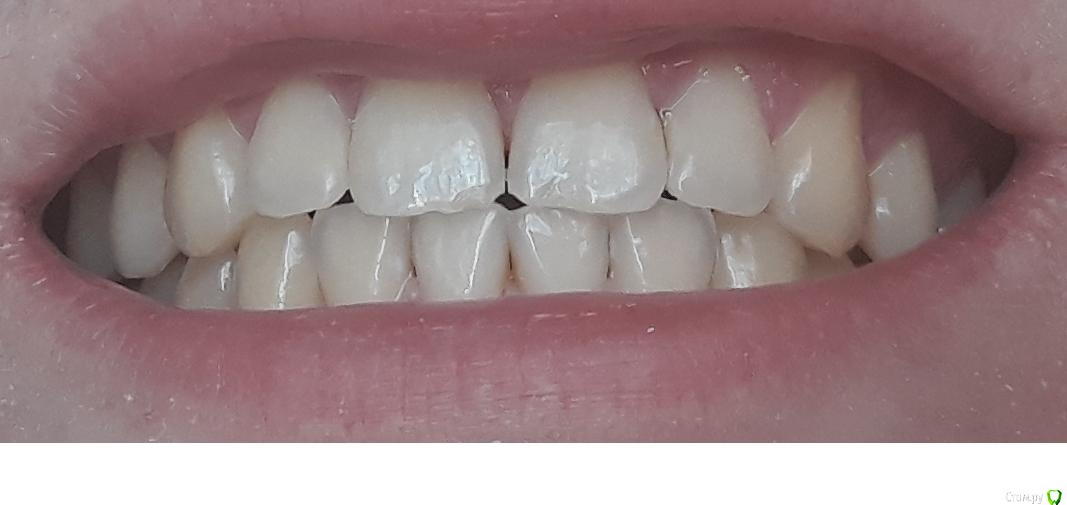

dentikl Опубликовано 25 января, 2019 Поделиться Опубликовано 25 января, 2019 Еще интересует один вопрос, если можно считать его корректным: можно ли было избежать появления трещинки? образовалась именно в ходе лечения.,Увы,нет.Просьба к Вам-выложите фото передних зубов(крупно) Ссылка на комментарий

ВиталийВиталий Опубликовано 26 января, 2019 Автор Поделиться Опубликовано 26 января, 2019 ,Увы,нет.Просьба к Вам-выложите фото передних зубов(крупно)надеюсь это то, что нужно Ссылка на комментарий

dentikl Опубликовано 26 января, 2019 Поделиться Опубликовано 26 января, 2019 надеюсь это то, что нужнопредполагаю,что Вы скрежещете зубами по ночам(бруксизм) и трещины должны быть на многих зубах. Ссылка на комментарий

ВиталийВиталий Опубликовано 26 января, 2019 Автор Поделиться Опубликовано 26 января, 2019 предполагаю,что Вы скрежещете зубами по ночам(бруксизм) и трещины должны быть на многих зубах.да, трещины есть и на нижних зубах. меньше, чем та, по которой Вы меня консультировали...и они вертикальные. по ночам нет бруксизма, но днем есть, Вы правы... Ссылка на комментарий

DmitrySH Опубликовано 26 января, 2019 Поделиться Опубликовано 26 января, 2019 Семечки лучше пальцами очищайте, они постепенно стирают эмаль. А зуб лечить не надо. просто наблюдать. 1 Ссылка на комментарий